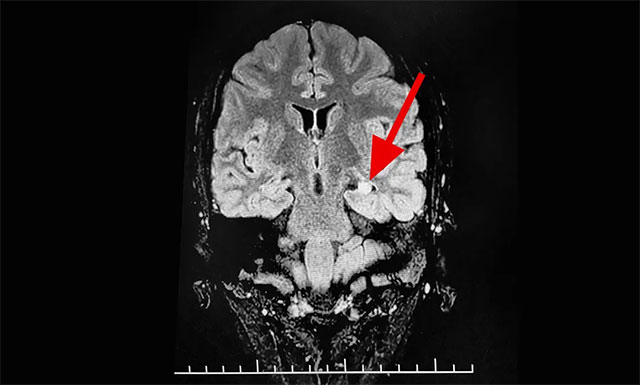

▲ 通過(guò)系列檢查最終明確患者致癲灶

來(lái)到該院后,醫(yī)院腦電監(jiān)測(cè)崔麗華主任應(yīng)用先進(jìn)的美國(guó)尼高力長(zhǎng)視頻腦電圖儀為玲玲做了24小時(shí)腦電監(jiān)測(cè)。崔麗華主任根據(jù)腦電圖監(jiān)測(cè)分析指出,患者玲玲顳區(qū)有癲癇波,左側(cè)較為嚴(yán)重。磁共振檢查后發(fā)現(xiàn),患者顳葉、海馬結(jié)構(gòu)異常。

上海藍(lán)十字腦科醫(yī)院功能神經(jīng)外科楊忠旭教授認(rèn)真查看了玲玲各項(xiàng)檢查報(bào)告,并聽取相關(guān)病情匯報(bào)后指出,一般幼時(shí)突發(fā)高熱驚厥,尤其伴有抽筋的癥狀,會(huì)導(dǎo)致大腦缺血、缺氧,而海馬對(duì)這種情況的耐受較差,極易造成其內(nèi)的神經(jīng)細(xì)胞受損,時(shí)間長(zhǎng)了就會(huì)發(fā)展成海馬硬化,成年后,有近一半以上的病人會(huì)因此患上頑固性癲癇。

玲玲癲癇診斷明確,系統(tǒng)內(nèi)科藥物治療不佳,確診為:難治性癲癇。應(yīng)用現(xiàn)代神經(jīng)影像學(xué)技術(shù)和電生理監(jiān)測(cè)技術(shù),能準(zhǔn)確定位導(dǎo)致癲癇發(fā)作的“責(zé)任病變”,手術(shù)指征明顯,未見明顯手術(shù)禁忌癥。楊教授為她制定了周全的手術(shù)方案并做好充分準(zhǔn)備。